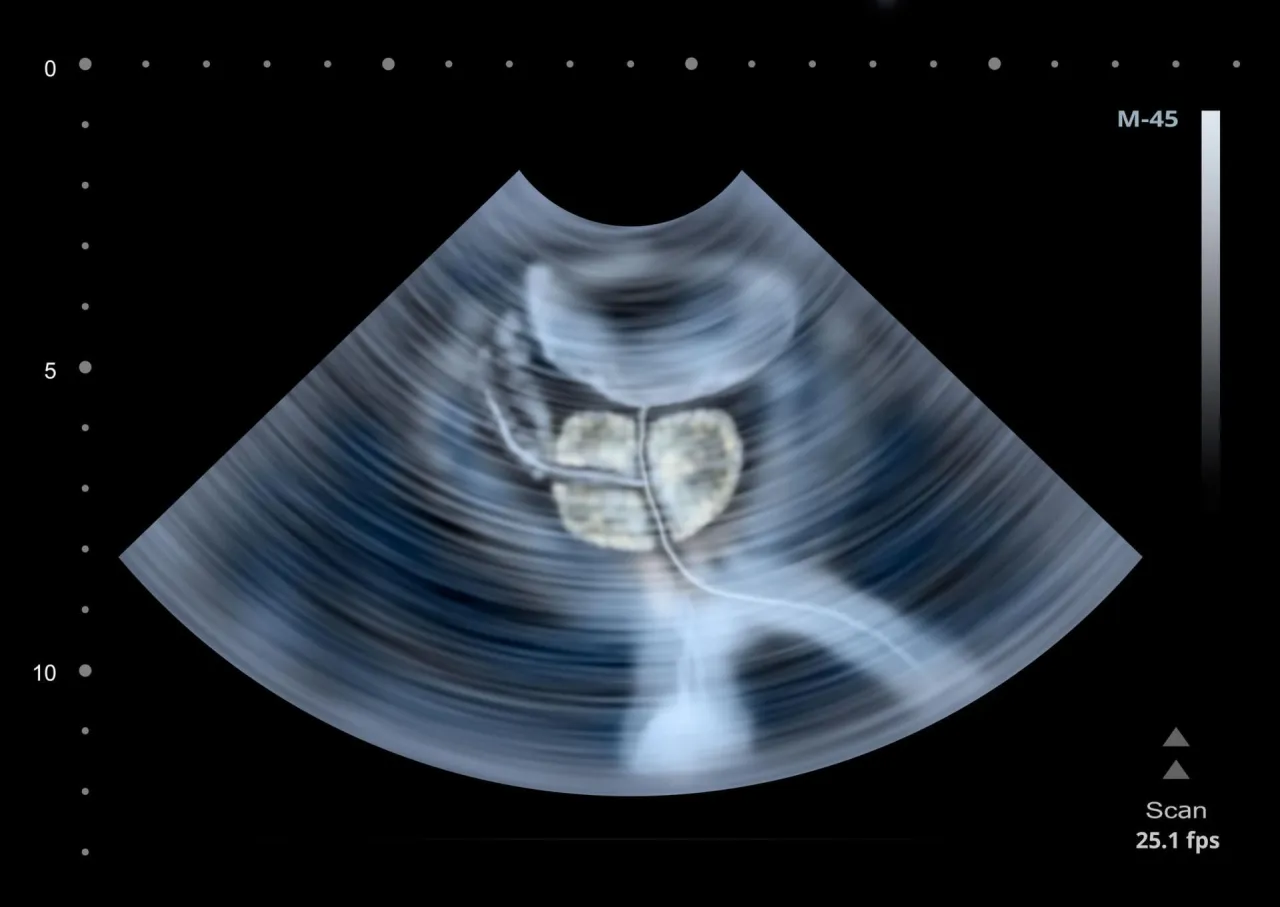

USG jamy brzusznej a USG transrektalne (TRUS) czym się różnią?

W diagnostyce prostaty wykorzystujemy dwa główne typy badań ultrasonograficznych. USG przezbrzuszne to standardowe badanie, które pozwala ocenić ogólną objętość prostaty oraz stan pęcherza moczowego. Jest nieinwazyjne i często wykonywane jako badanie wstępne. Natomiast USG transrektalne (TRUS) jest znacznie dokładniejsze. Wykonuje się je poprzez wprowadzenie specjalnej głowicy USG do odbytnicy, co umożliwia bardzo precyzyjną ocenę struktury gruczołu krokowego, wykrycie nawet niewielkich zmian i jest często wykorzystywane przy podejrzeniu raka, np. do celowanego wykonania biopsji.